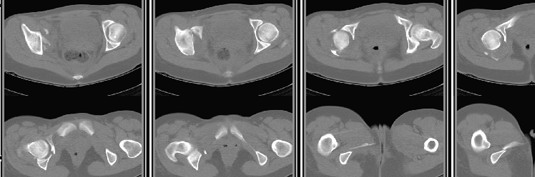

30/11/04 |  30/11/04 |  30/11/04 |  14/12/04 |  14/12/04 |  14/02/05 |  14/02/05 |  21/02/05 | Уважаемые коллеги! Случилось вторичное смещение вертлужной впадины после операции. Посоветуйте, что делать. Пациентка 18 лет. Травма 19.11.04. D.s.: Закрытыый Т-образный высокий перелом правой вертлужной впадины. Закрытый перелом м\мыщелкового возвышения левой б\берцовой кости. 9.12.04 операция - открытая репозиция, остеосинтез переломам вертлужной впадины. 30.12.05 выписаны на амбулаторное лечение с рекомендациями не вставать на правую ногу. 14.02.05 при контрольном осмотре на Р-граммах выявлено вторичное смещение передней колонны. Клинически подвывиха нет, имеется умеренная приводящая контрактура правого тазобедренного сустава, гипотрофия мышц н\конечностей. Госпитализирована в травмотделение. Выполнено КТ. Имеется смещение передней колонны кнутриЮ диастаз 8 мм. Посоветуйте пожалуйста, что предпринять в данной ситуации.

У больной имеется диастаз лонных и седалищных костей, то есть "разорвано" тазовое кольцо. В перспективе возможно образование ложного сустава на уровне основания лонной кости с болевым синдромом, поскольку седалищная кость не срастется.

Сустав-то как раз неплох, поскольку впадина почти вся конгруэнтна, по крайней мере вся нагружаемая часть, и подвывиха бедра нет. Артроз в перспективе тут, конечно, не исключить, но на первом плане проблема целости тазового кольца, т.е. нестабильное несращение, о чем А. Рунков писал. На седалищной дефект, и если и разошедшееся основание лонной не срастется, то болезненные проявления могут быть сразу после начала нагрузки, как ее не отсрочивай.